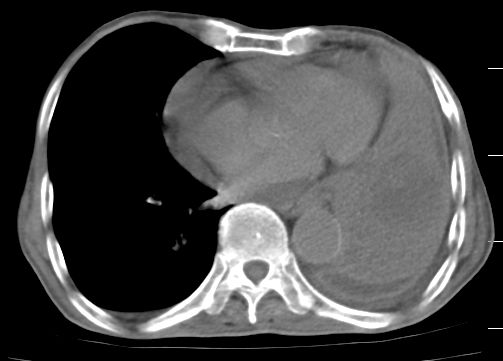

标题: CT10141:男、84岁,咳嗽、咯血1年。 [打印本页]

标题: CT10141:男、84岁,咳嗽、咯血1年。

支持左侧中央型肺癌伴下叶肺不张\\纵隔淋巴结转移.左侧包裹性胸腔积液\\心包积液.左侧少量胸腔积液..慢性支气管炎伴部分间质纤维化.

咯血病史较长,左肺下叶实变,体积未明显缩小,隐约可见血管影及坏死阴影,双肺门及纵隔淋巴结增大,心包增厚积液,纵隔右移位,单侧胸腔积液,首先考虑:大叶型肺泡癌伴纵隔心包转移。

左肺中心性肺癌并左肺下叶肺不张,纵隔淋巴转移、同侧胸腔及心包积液(转移)。